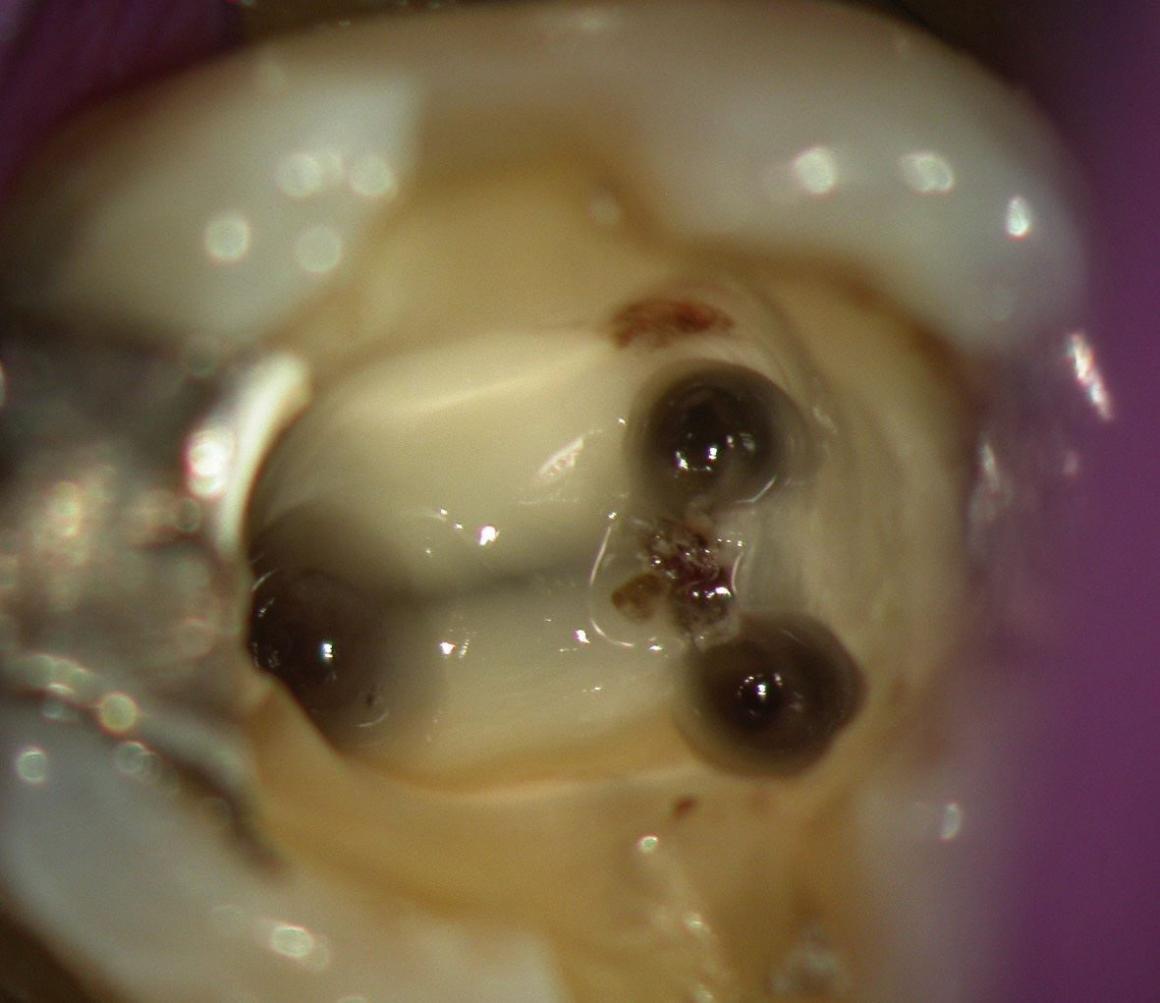

Unter örtlicher Betäubung ist die Behandlung meist schmerzfrei. Nach Entfernung der Karies und nach der Schaffung eines Zugangs in den Zahn werden die Kanaleingänge dargestellt und die Länge jedes einzelnen Kanals wird möglichst exakt unter Anwendung von Röntgen oder elektrometrischer Längenmessung bestimmt. Abhängig vom zu behandelten Zahn kann die Anzahl der Kanäle stark variieren.

Danach erfolgt die Aufbereitung mit Hilfe von speziellen, sehr feinen Instrumenten aus einer Nickel-Titan-Legierung oder Edelstahl und kann manuell oder maschinell erfolgen. Zusätzlich können Ultraschalinstrumente oder Laser benutzt werden.

Danach werden die Kanäle gereinigt und so ausgeformt, dass später eine dichte Wurzelfüllung möglich ist. Für eine möglichst vollständige Reinigung des Kanalsystems wird die mechanische Aufbereitung durch Spülungen mit desinfizierenden Lösungen ergänzt.